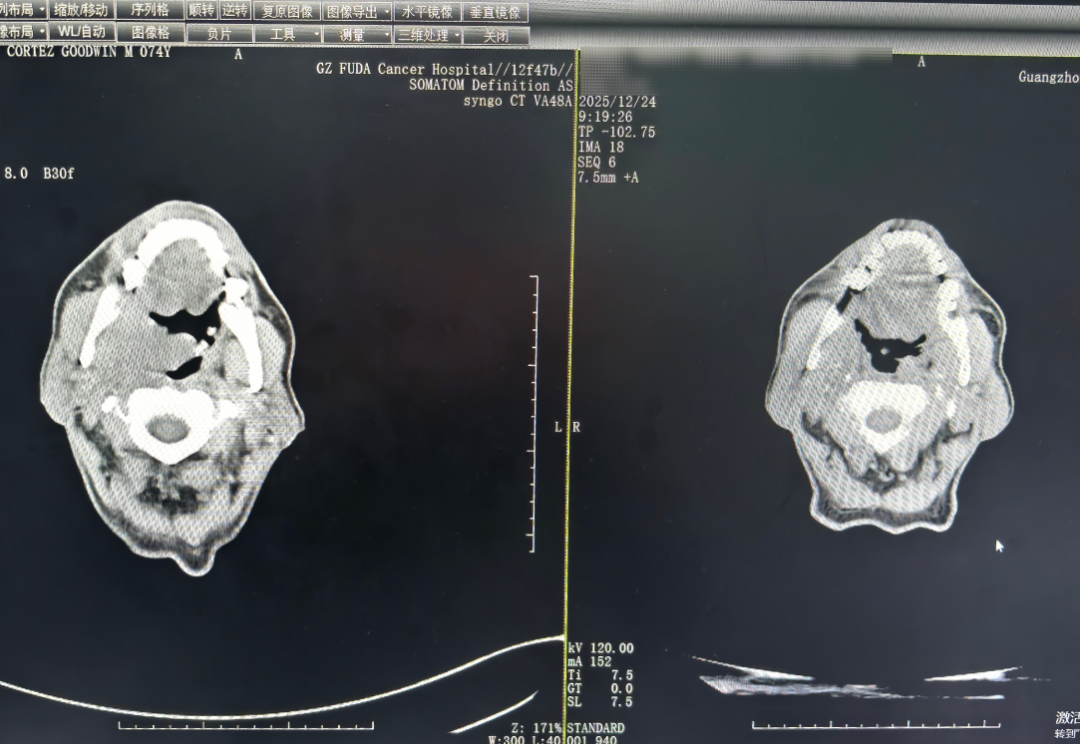

在复大,详细检查显示:肿瘤已侵犯到鼻咽、软腭及右侧肌肉,且伴发出血风险。医疗团队没有采用传统大开刀的方式,而是为他量身制定了一套“组合方案”:通过动脉灌注化疗精准攻击肿瘤,并用介入栓塞术封堵血管、降低出血可能;同时配合静脉滴注PD-1抑制剂,重新激活免疫系统识别和杀伤肿瘤细胞的能力,去对抗癌细胞。

△两个疗程后的CT对比图,口咽肿物、颈部肿块缩小